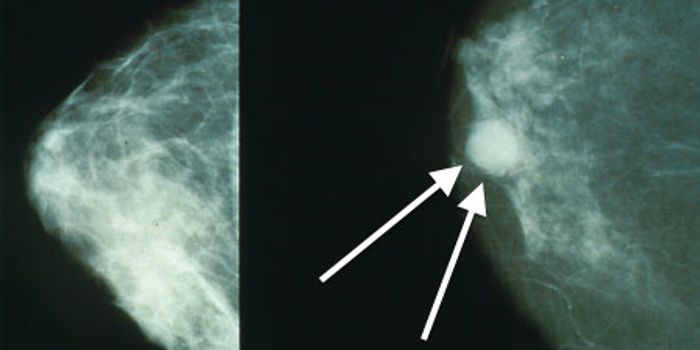

APR 01, 2022Clinical & Molecular DXA mammogram is an x-ray image of the breast that can reveal early signs of breast cancer. Screening mammograms ...

MAR 03, 2016Clinical & Molecular DXWhen one of the country’s top groups representing the interests of women’s health care physicians puts out a ...